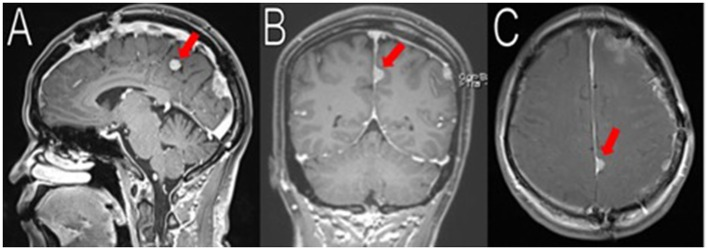

圖1,初始成像顯示多發(fā)睪丸素瘤。術(shù)前對(duì)比T1和T2 MRI掃描顯示多發(fā)性腦膜瘤。左側(cè)鈣化的鐮旁分葉狀腫塊(2 * 2.2 * 3.3 cm, AP, TV, CC)伴血管源性水腫(A,B, D-E中紅色箭頭)。左側(cè)額顳凸區(qū)有4.5×2.9×4.1 cm (AP, TV, CC)腫塊,其上有2.3×2.0×1.9 cm (AP, TV, CC)腫塊(B-F中黑色箭頭)。枕葉腫物測(cè)得2.6×2.9×3.9 cm (AP, TV, CC) (A,B,E中白色箭頭)。向右中線有8毫米的偏移。圖像提示2型神經(jīng)纖維瘤病。